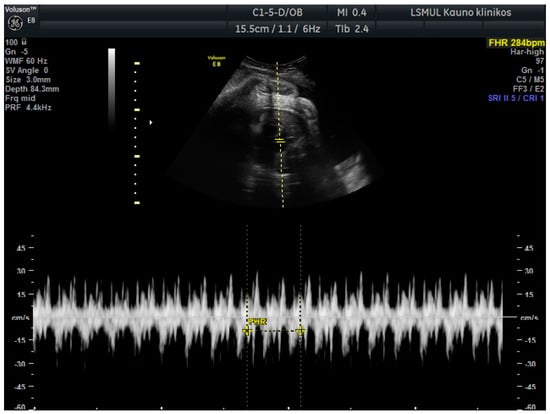

A 34-year-old gravida 3, para 1, aborta 1, noted a loss of fetal motion at 34 weeks of gestation. A two-dimensional ultrasound showed fetal supraventricular tachycardia (fetal heart rate: 284 bpm), signs of fetal hydrops—ascites, pleural and pericardial effusion (Figure 1 and Figure 2). No cardiac or other structural fetal anomalies were found, as well as no anemia—middle cerebral arterypeak systolic velocity was 29 cm/s. We report on a male fetus, biometrical data adequate to gestational age. Electronic fetal heart rate monitoring failed to track the FHR due to its rapidity. The patient had a history of laboratory confirmed influenza at 30 weeks of gestation and was treated with oseltamivir. She gave birth to a healthy boy five years ago.

Figure 1. Fetal supraventricular tachycardia.